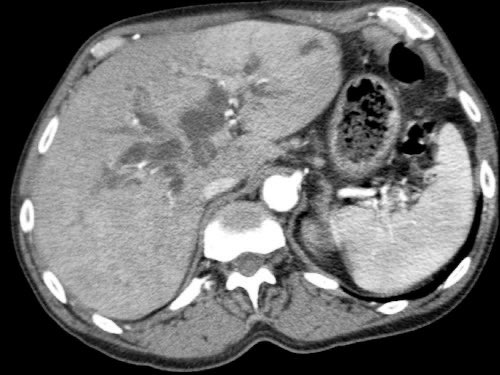

Tái tạo mặt phẳng coronal cho thấy:

- Bất thường bờ viền thành SMV được nhận thấy rõ hơn trên tái tạo coronal này (mũi tên).

- Khối u ở thân tụy (đầu mũi tên trắng).

- Huyết khối trong các nhánh bên của SMV (mũi tên xanh nhỏ).